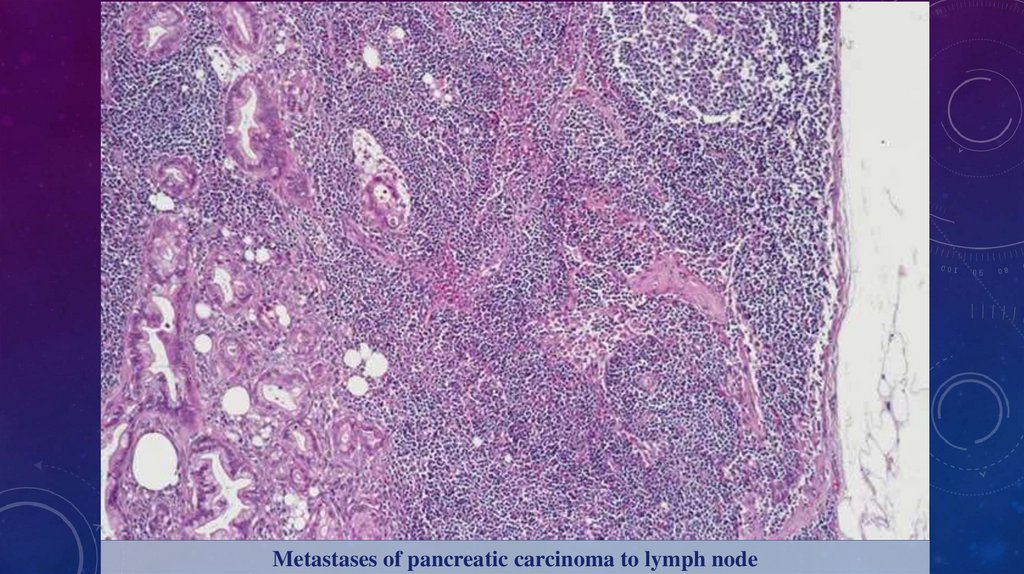

Метастази

Метастазування – це віддалене місце росту пухлини, не

пов'язане з первинною пухлиною; внаслідок поширення

пухлинних клітин через рідини організму (кров, лімфу) або

порожнини.

Метастазують злоякісні пухлини, але дуже рідко доброякісні

пухлини також можуть метастазувати.

Шляхи метастазування:

1. Лімфогенно по лімфатичних судинах в регіонарні лімфатичні

вузли, після – у віддалені лімфатичні вузли.

2. Гематогенно через кровоносні судини до віддалених органів.

3. Імплантація (контактні) через порожнини тіла.

Metastases of pancreatic carcinoma to lymph node